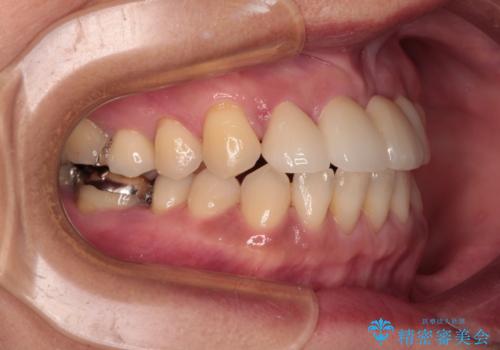

矯正治療により前歯横幅のバランスを整えた後に、上顎前歯をオールセラミックブリッジにて補綴治療を行うこととしました。

舌突出癖により、上下前歯が突出して離開してしまったため、舌のトレーニングを徹底的に行いました。